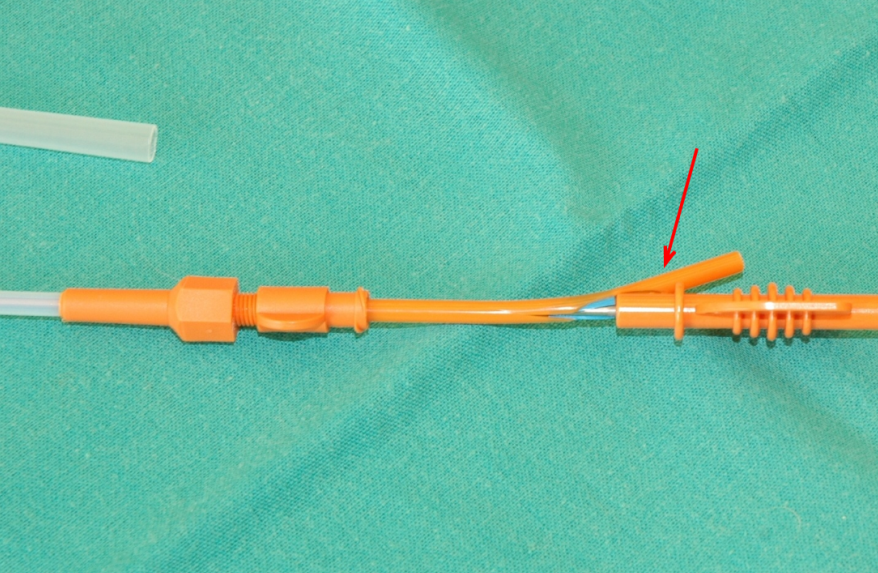

Процесс стентирования проводится под эндоскопическим и радиологическим контролем и занимает 10–20 минут. В зависимости от тяжести состояния, в котором был доставлен пациент в клинику, он остается в стационаре от 1 до 2 суток. Первые 14 дней животное получает стандартную схему антибиотиков, противокашлевые препараты, муколитические средства, а в некоторых случаях – стероиды. Приблизительно через 21 день нитиноловая сетка заполняется прорастающим эпителием трахеи, и стент полностью фиксируется в трахее.

По состоянию животного проводятся контрольные рентгенологические обследования через 4 недели. Далее — 1 раз в 6 месяцев.

Нитиноловый стент DEXTRONIX после установки